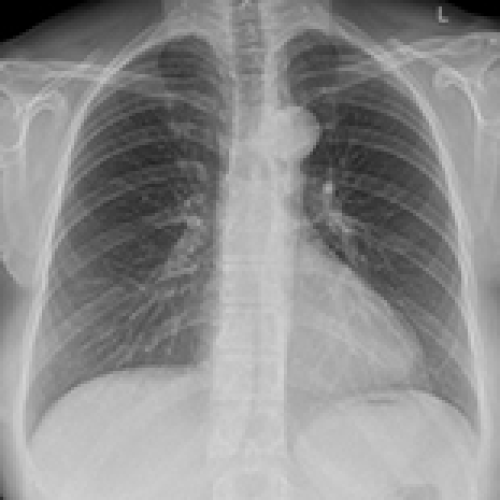

14 Sep 2021 : Database Analysis

Chest Radiological Findings and Clinical Characteristics of Laboratory-Confirmed COVID-19 Patients from Saudi Arabia

Rowa Aljondi, Salem Alghamdi, Abdulrahman Tajaldeen, Ikhlas Abdelaziz, Lubna Bushara, Hind A. Alghamdi, Hassan Alhinishi, Bandar Alharbi, Raied Alshehri, Abdullah Aljehani, Mansour Almotairi

DOI: 10.12659/MSM.932441

Med Sci Monit 2021; 27:e932441

3,434 1,332 0

3434 1332 0